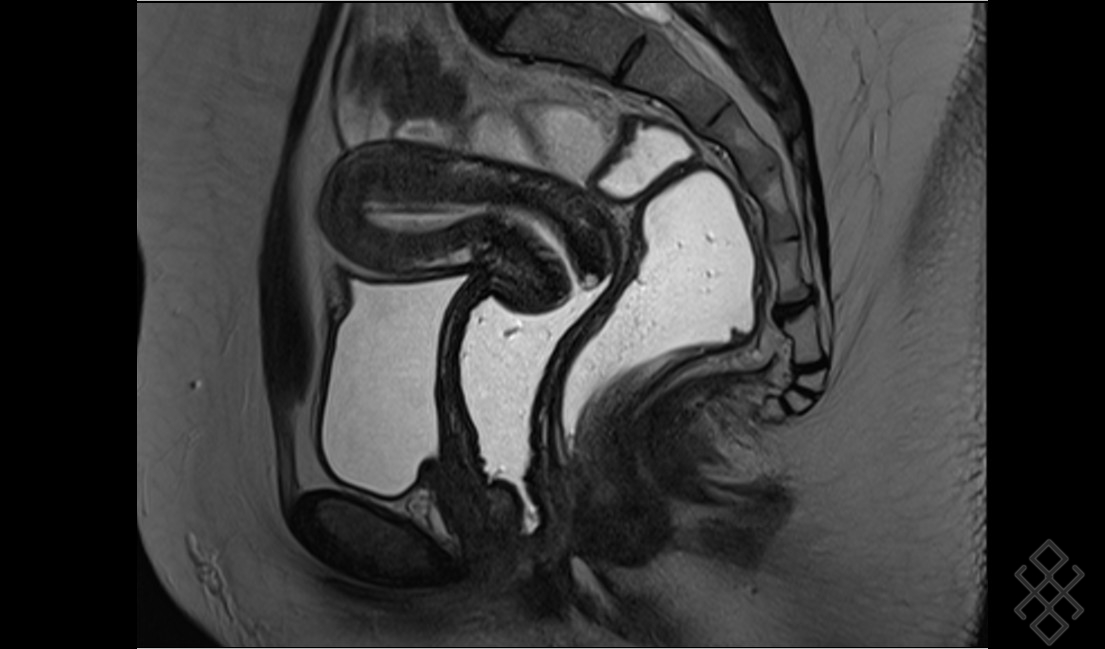

IRM pelvienne L'IRM est un examen non irradiant, sans risque, qui est très utile pour le diagnostic et le bilan d'une endométriose puis Comment se déroule l'examen IRM pelvienne dynamique ?

Dans la plupart des cas d'IRM pelvienne, vous devrez faire un lavement évacuateur quelques heures avant l'examen Comment faire un lavement Evacuateur ? Un lavement évacuateur consiste à injecter par l'anus un liquide dans le rectum ou l'extrémité du. Une préparation digestive par lavement rectal (Microlax) est recommandée afin d'améliorer la qualité des images.

PPT IRM PELVIENNE Pour les nuls PowerPoint Presentation ID5221314. Quels organes Voit-on sur un IRM pelvien ? Qu'est-ce qu'une IRM pelvienne Comment se préparer à une IRM pelvienne ? "En fonction de la demande faite par le médecin généraliste ou spécialiste, le radiologue décidera s'il est nécessaire d'effectuer un lavement évacuateur quelques heures avant l'examen, s'il faut être à jeun (généralement six heures avant l'examen) ou s'il faut avoir une vessie pleine ou vide", répond la spécialiste.

MA 1ERE IRM PELVIENNE ENDOMETRIOSE YouTube. Il est conseillé de réaliser un lavement rectal à domicile au Normacol, idéalement 1 à 3h avant l'examen si possible du Microlax et éventuellement du produit de contraste gadoliné en fonction de l'indication de l'IRM pelvienne.